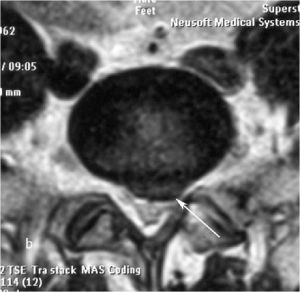

Рис. 8a,b. Магнитно-резонансная томография (МРТ) поясничного отдела позвоночника в сагиттальной (a) и аксиальной (b) проекции. Стрелкой показана мп секвестрированная парамедианная грыжа диска L5-S1 слева.

Рис. 9a. Магнитно-резонансная томография (МРТ) поясничного отдела позвоночника в сагиттальной (a) и аксиальной  (b) проекции. Стрелкой показана мп секвестрированная парамедианная грыжа диска L5-S1 слева. Рис. 9b. Магнитно-резонансная томография (МРТ) поясничного отдела позвоночника в сагиттальной (a) и аксиальной  (b) проекции. Стрелкой показана мп секвестрированная парамедианная грыжа диска L5-S1 слева.

При рентгенографии (Рис.7) и МРТ (Рис.8) поясничного отдела позвоночника выявляется дегенеративный ретролистез L5 позвонка, секвестрированная  парамедианная грыжа мп диска L5-S1  слева.